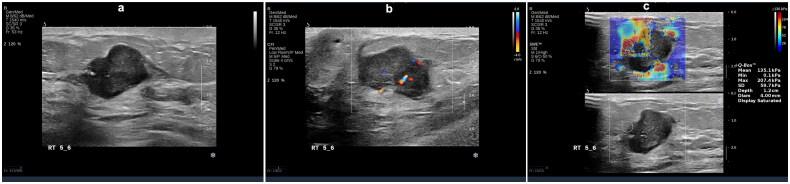

We performed a retrospective analysis encompassing 310 young women with breast cancer. Observations were made regarding the ultrasonography and elastography characteristics of the identified breast lesions. Subsequently, based on immunohistochemistry results patients were classified into five distinct molecular subtypes: luminal A, luminal B (HER2-), luminal B (HER2+), HER2+, and triple-negative breast cancer (TNBC). Clinical, pathological, and ultrasound imaging features were compared among these subtypes using binary logistic regression analysis.

Statistically significant differences were observed in various parameters across the five molecular subtypes ( < 0.05), including tumor size, morphology, margins, calcification, posterior echo features, blood flow (Adler grading), and tumor hardness. Specifically, luminal A subtype exhibited propensity for spiculated margins, lower blood flow grading, and decreased hardness; luminal B subtype was characterized by angular margins; HER2+ subtype manifested higher blood flow grading, calcification, and elevated hardness. Conversely, TNBC subtype displayed smooth margins, absence of calcification, and heightened hardness.

Specific molecular subtypes of breast cancer have unique ultrasonic and elastic imaging characteristics.